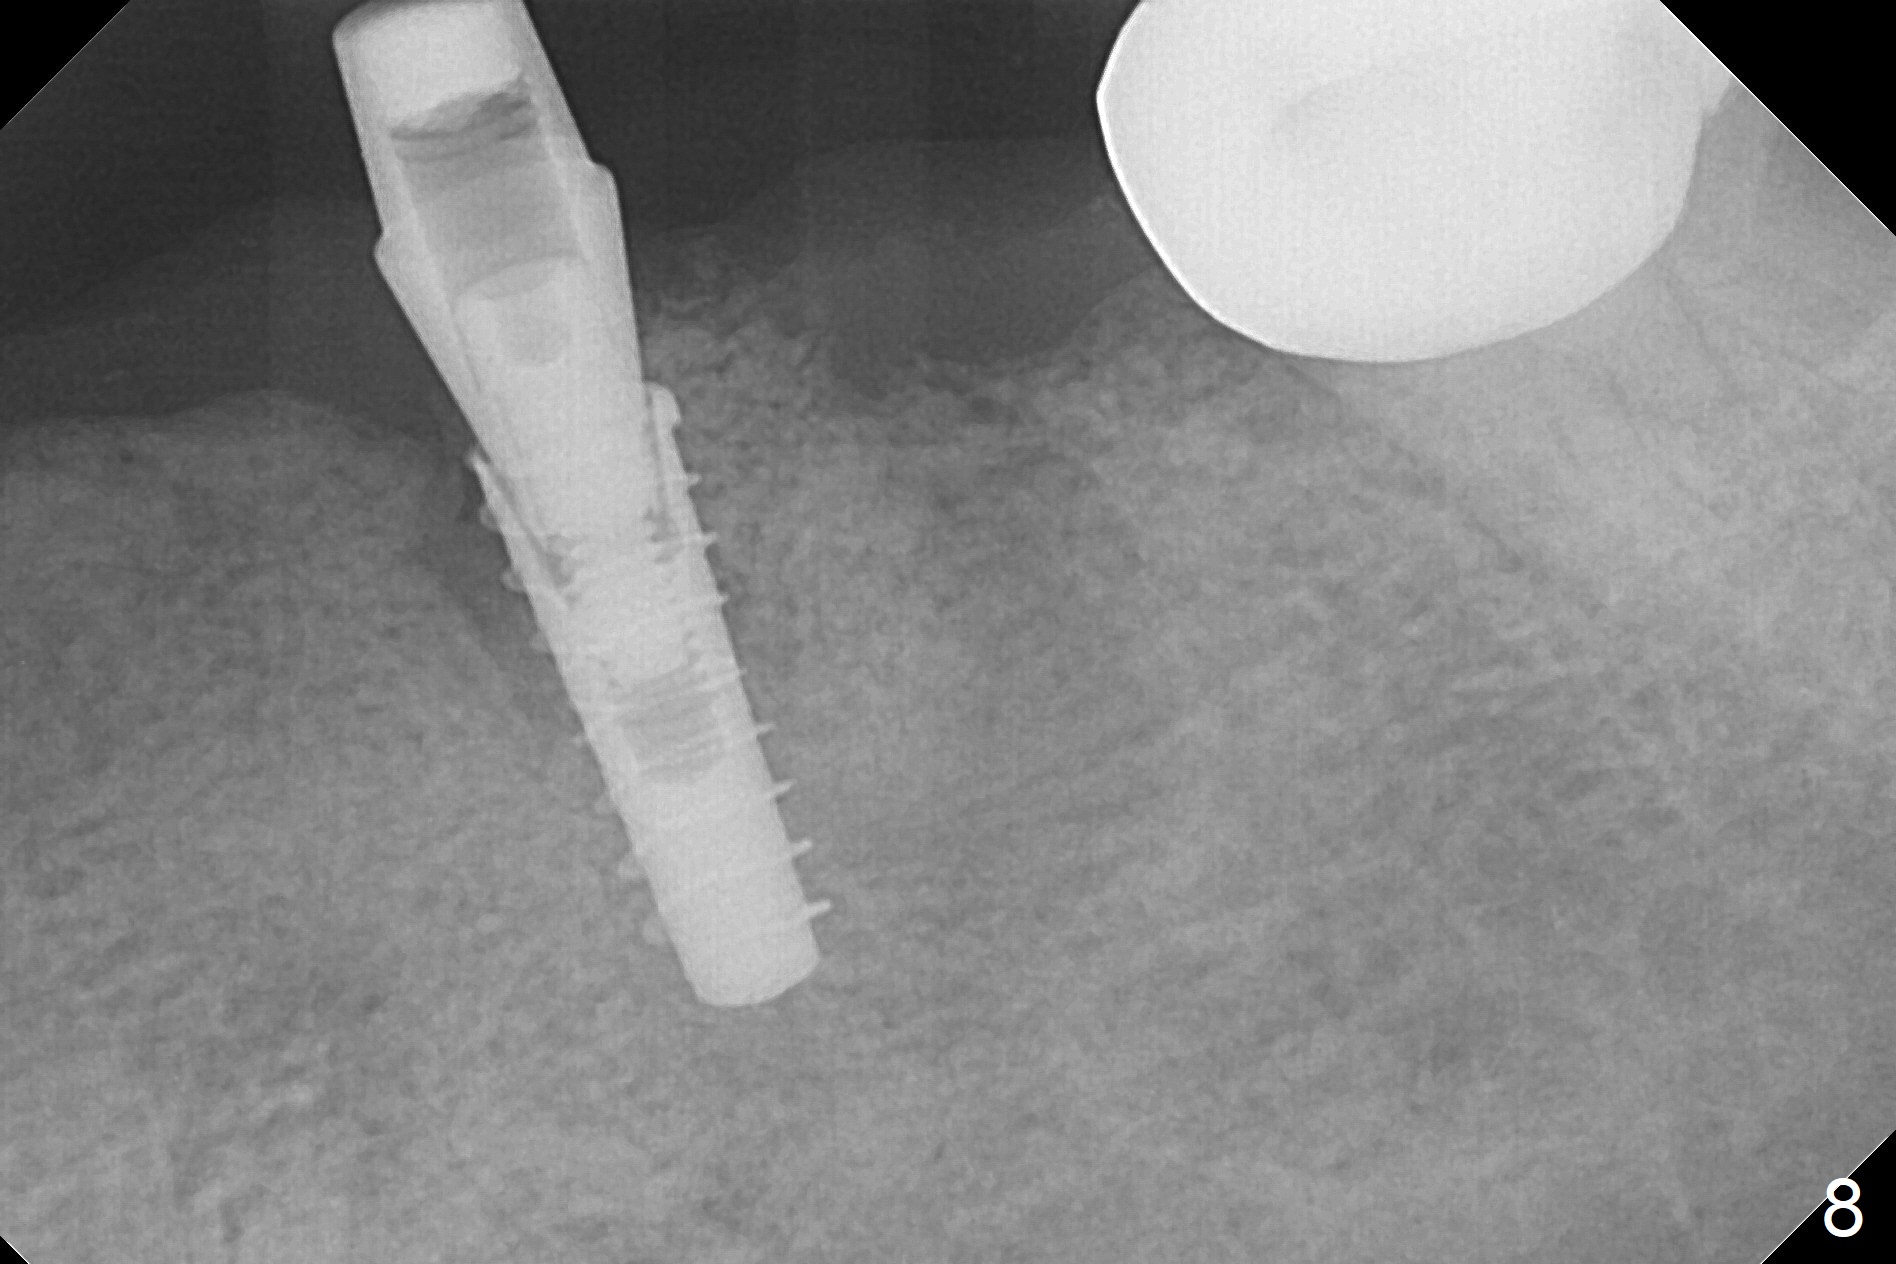

After removal of the pontic at #19 and retainer at #20 (Fig.1) and of vertically fractured root, the buccal plate is found to be defective (Fig.2 *). An implant will be placed as lingual as possible. Since the apex of the affected tooth is coronal to the Mental Loop (Fig.3 red dashed line), an osteotomy (Fig.4 yellow arrow) to be established in the mesial slope (blue dashed line) after extraction (black area) appears to be safer than that along the long axis of the tooth. The initial osteotomy is accomplished by free hand (Fig.5), but when the lower RPD is inserted, the superior end of the 1.5 mm pilot drill is distal (Fig.6). When the trajectory is corrected using the RPD as a surgical guide at the same depth (17 mm gingival level), brisk hemorrhage is from the osteotomy without severe pain. After hemostasis is achieved by packing the socket with Osteogen plug and bone graft and packing bone graft into the osteotomy, 3.3 mm Magic Drill is used for 14 mm. A 4x11 mm IBS implant is placed with 60 Ncm (Fig.7). The implant is then placed deeper, followed by placement of a 4.5x4(3) mm abutment and further bone graft (Fig.8). Finally the implant/abutment complex is apparently in an acceptable mesiodistal position with a large buccal gap which has been filled by bone graft (Fig.9 *). In fact the Mental Loop seems to have been not violated in the procedure (Fig.10). X-ray is taken 3 and 6 months postop. Bone graft (Fig.11,12 (CBCT) *) appears to remain over the buccal (B) surface of the implant coronally 13 months postop (7 months post cementation). The gingiva at #19 and 20 is apparently healthy 8 months post cementation except mild recession at #20 (Fig.13).